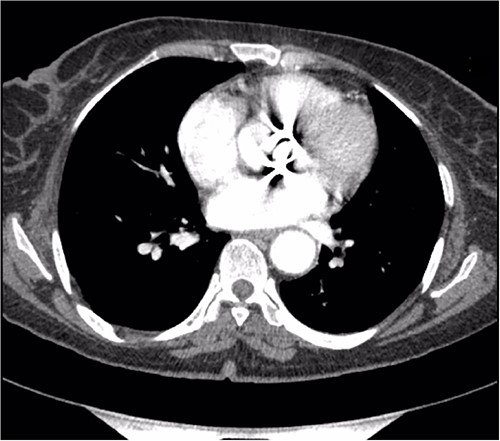

A thorough cardiovascular examination was performed, which revealed normal prosthetic valve clicks and a grade 3 ejection systolic murmur in the right second parasternal space. Further investigations included a transesophageal echocardiogram (TEE), which showed a paravalular anechoic free space around the prosthetic mechanical aortic valve with paravalular leakage and regurgitant flow with dehiscence of the prosthesis causing aortic stenosis (Fig. 1). A computed tomography (CT) scan was also performed to rule out aortic calcification, which revealed a normally seated aortic valve prosthesis with no visualization of the paravalular free space (Fig. 2). During the preoperative workup, blood cultures showed bacterial growth of Brucella melitensis. A multidisciplinary team approach was initiated, and the patient was started on antimicrobial therapy with gentamicin, doxycycline and rifampin. However, due to the patient developing abnormally high levels of Aspartate aminotransferase (AST) and Alanine aminotransferase (ALT), which is a side effect of rifampin, the regimen was changed to ceftriaxone, doxycycline and trimethoprim/sulfamethoxazole.

Preoperative CT demonstrating a previous aortic mechanical valve prosthesis.